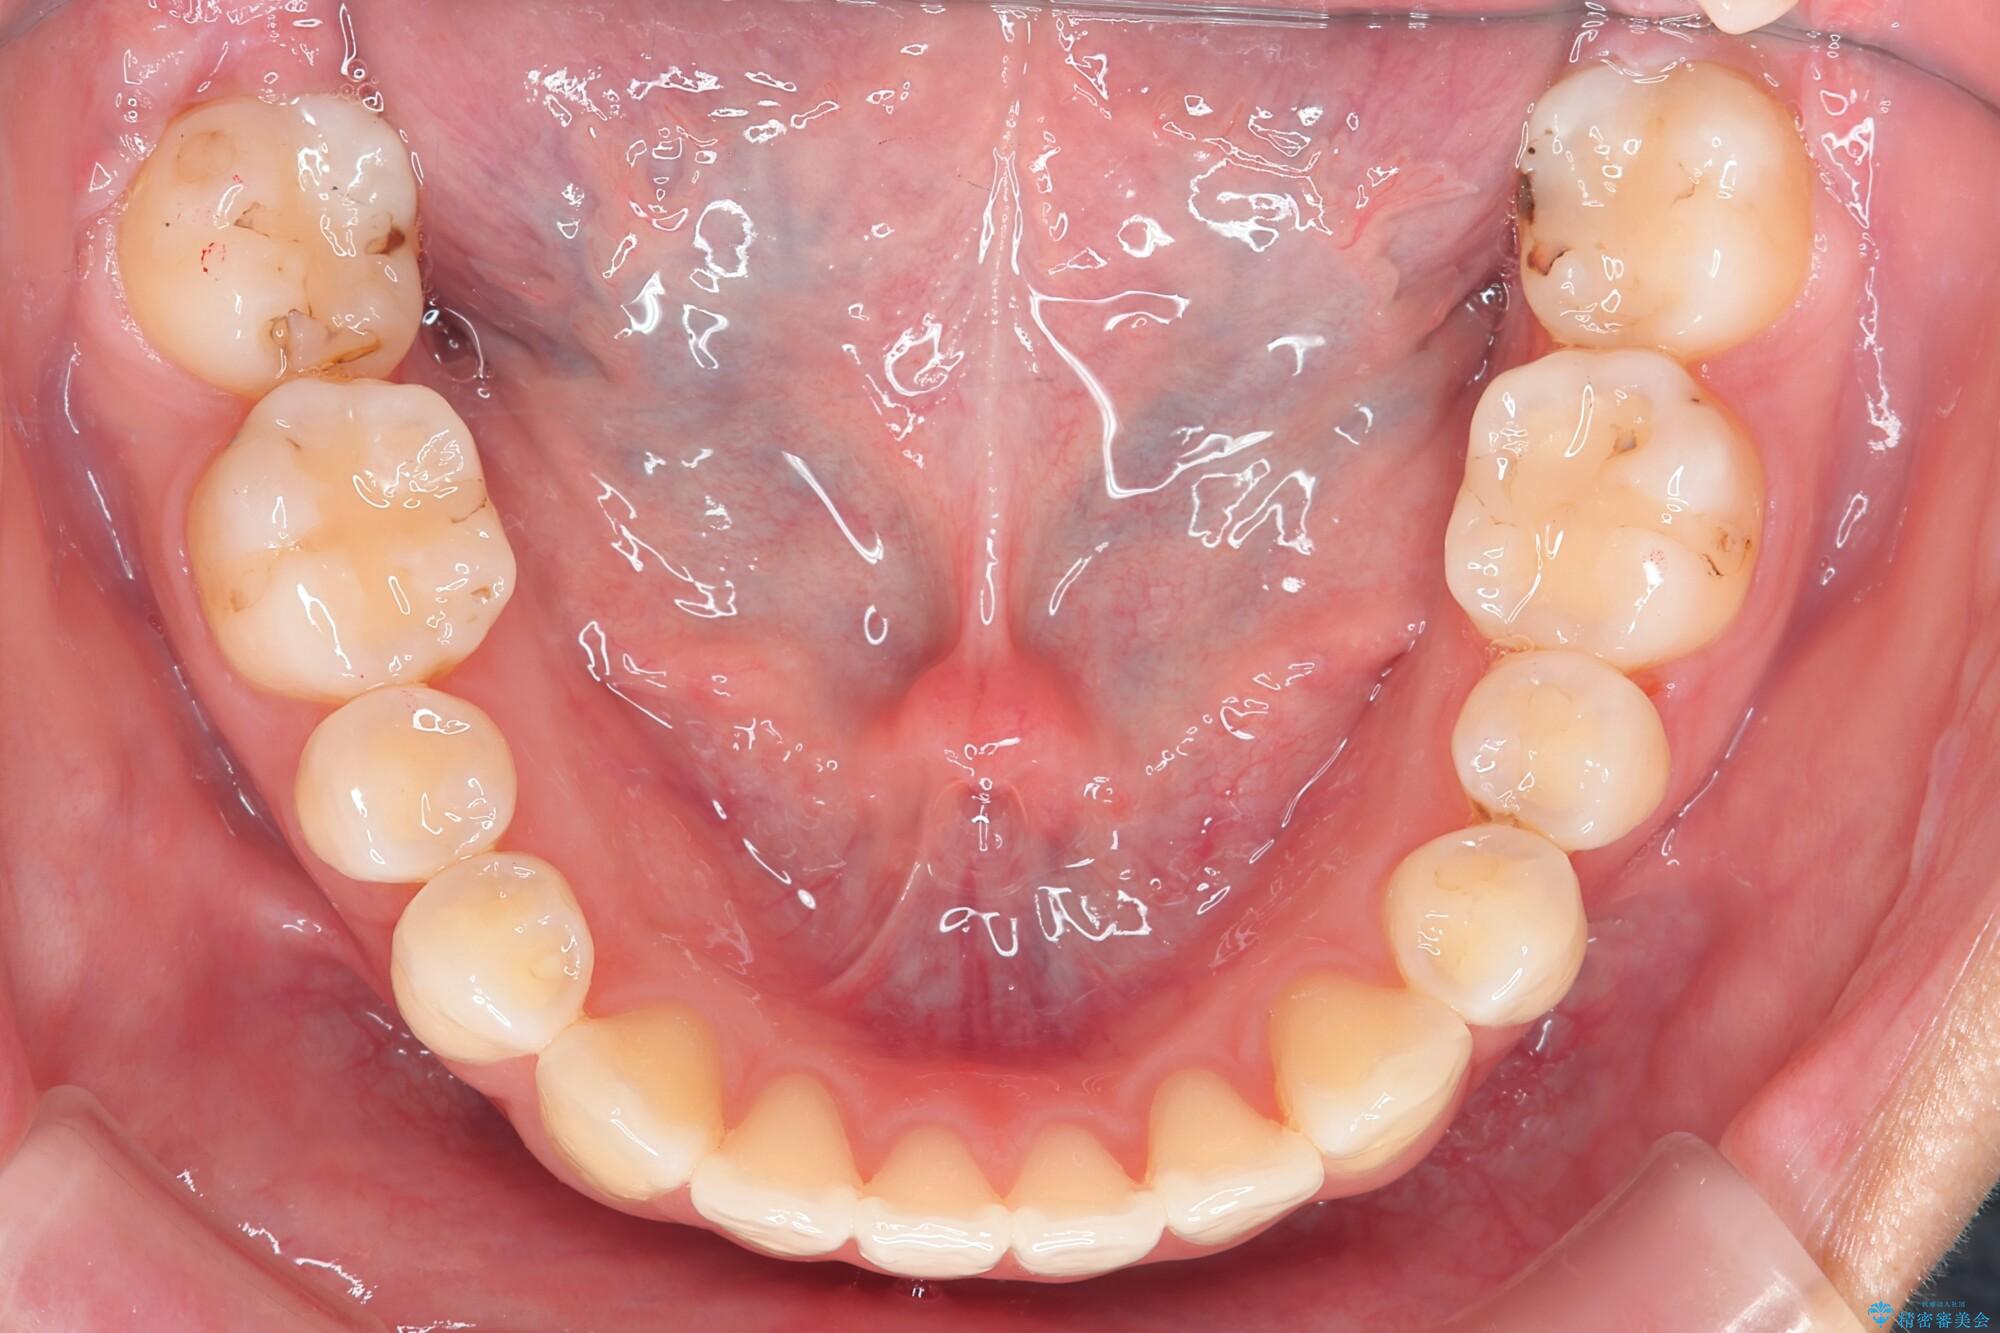

噛まない前歯と捻じれてしまった歯を改善したいと、矯正治療を希望された患者様です。

マルチブラケットを用いた非抜歯のワイヤー矯正で噛み合わせと歯並びを改善していきます。

1年で歯並び、嚙み合わせともにしっかりと改善されました。

患者様にも、非常に噛みやすくなったと喜んでいただくことができました。